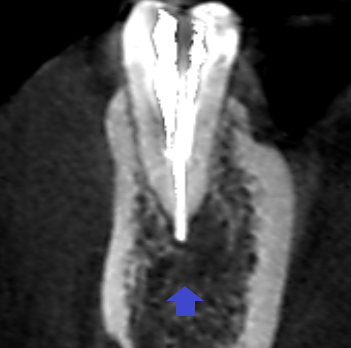

下顎第二小臼歯の初診時の冠状断のCT画像です。

赤い矢印の先に膿の影がみられます。膿は、画像では右側の舌側で拡がっていました。